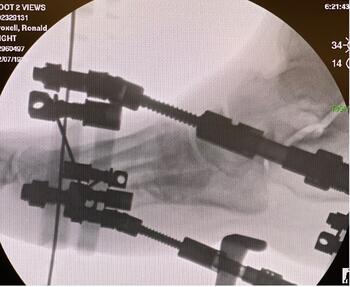

We then assembled and affixed a Stryker butt frame to the right lower extremity. Utilizing the concept of the butt frame along with the dynamic struts, we achieved stability to the rearfoot and further dialed in the correction of the forefoot utilizing the forefoot ring and struts. The patient remained pain-free and was discharged home with home health and oral antibiotics per infectious disease recommendations. The goal was to have him remain in the external fixator for three months for consolidation and further soft tissue healing. Discoloration to the distal toes improved exponentially after surgical reduction, and the toes returned to a more normal appearance. The patient followed up routinely every week with further necrosis and soft tissue demarcation, especially at the dorsal aspect of the foot and the medial column. He underwent gradual, weekly debridement with further soft tissue demarcation and evidence of viability of the underlying tissue noted to the dorsum of the foot. However, the medial column gradually worsened, and at the five-week mark, there was exposure of the medial cuneiform bone. We decided to take him back to the operating room. Though the patient had been very adherent with his care, surgical debridement of the bone and potential hardware removal would be necessary.